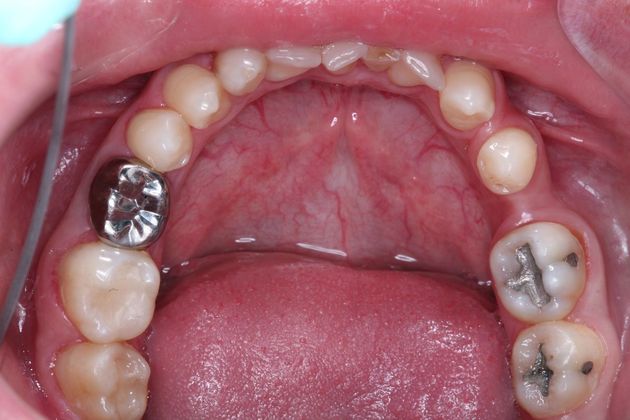

Full mouth rehabilitation. This 20 year old patient had emigrated from Bosnia only a few years earlier with his mother and two sisters after his father had perished in the Bosnian/Serbian conflict. He had severe hereditary dental dysplasia, with multiple retained baby teeth where permanent teeth never formed. He had a total of nine missing teeth, and the teeth that were present were not in their correct positions, leading to a poor bite relationship and multiple large gaps throughout his mouth. He was embarrassed to smile and wanted to know what could be done. His was a very complex case requiring Smile design and; the services of an oral surgeon to take out the baby teeth and strategically place implants at different times of his treatment, an orthodontist to level, straighten and create the proper size spaces for the placement of nine implants, gum sculpting, whitening, and the placement of fillings and crowns on natural teeth, and crowns on the nine implants. It took some time, but he got a great result and the resulting confidence has helped him go to college, get a better job and have a social life! Procedures: Smile design, oral surgery and implant placement, orthodontics, gum lift, whitening, fillings and crowns. TESTIMONIAL:" Dr. Balloch is a very skilled, compassionate and empathetic dentist who develops a personal relationship with his patients. He is (by far) the best dentist that I have experienced in my 85 years. His dental and office staff are equally friendly and professional. Dr.Balloch definitely exceeded my expectations. I highly recommend!"